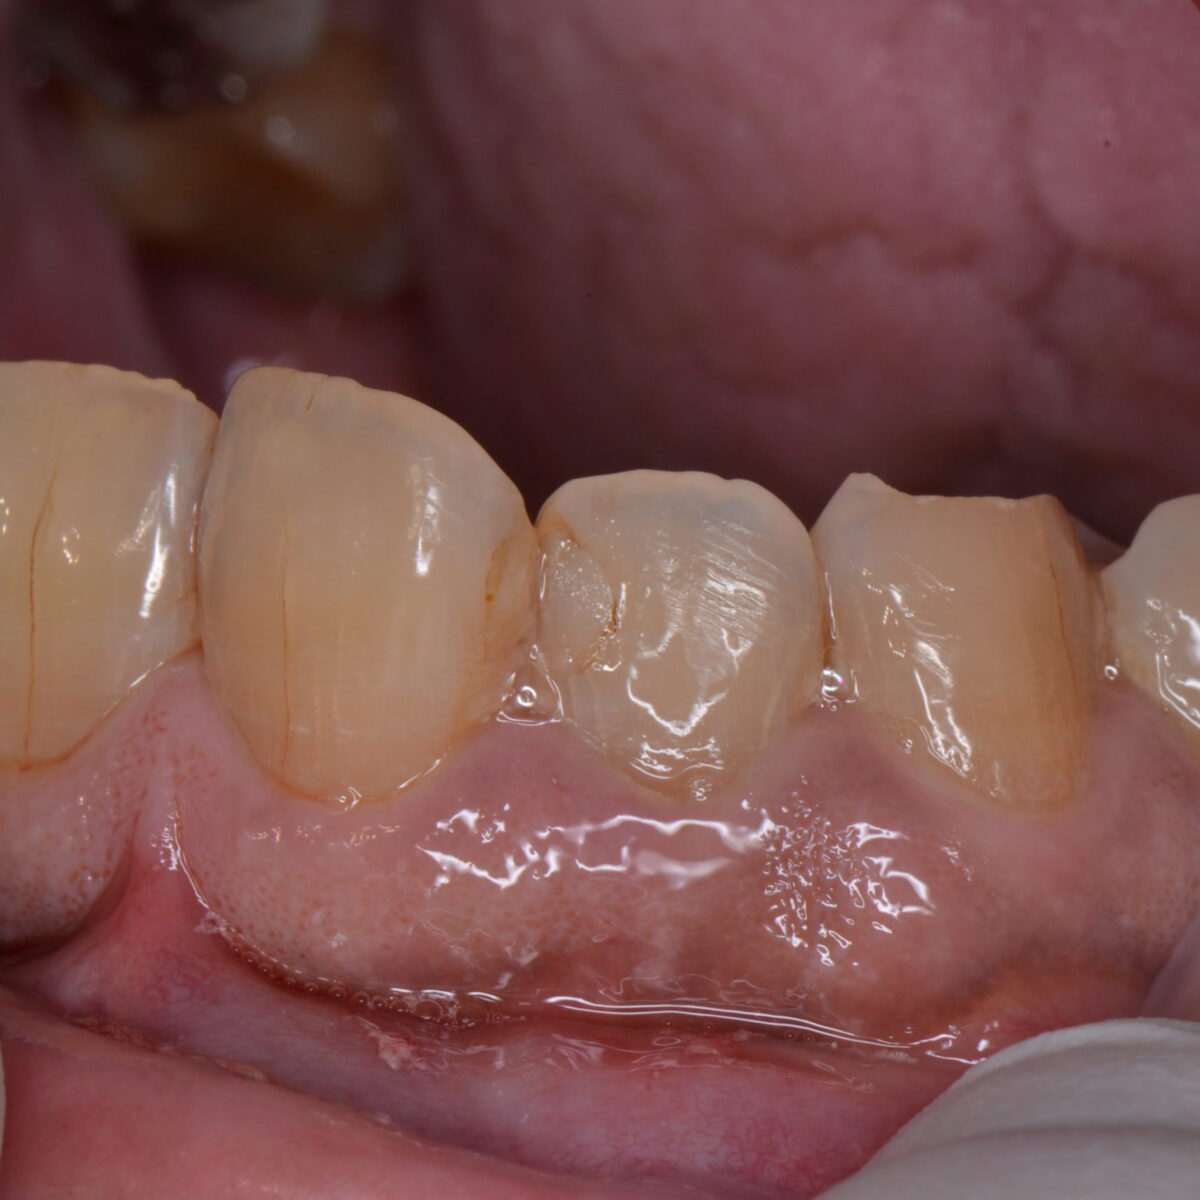

前歯のつめもの5

【東京メトロ東西線妙典駅 徒歩5分の歯医者】市川、妙典の歯科医院、めぐりデンタルクリニックの梶原です。 本日も治療の写真を載せたいと思います。外れたところをそのままにしていた方の治…